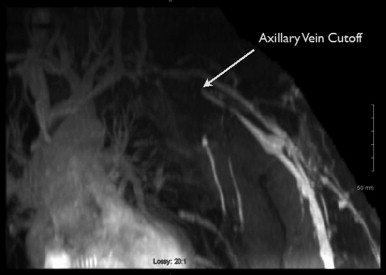

MRA

MRA is typically performed using gadofosveset trisodium (Ablavar®, Lantheus Medical Imaging, North Billerica, MA, USA). Gadofosveset trisodium stays in the blood pool longer, allowing high-resolution images of the lymph nodes and vasculature to be obtained. Both the donor site and recipient sites are imaged. Donor site imaging provides information on the vascular anatomy as well as the quantity and location of lymph nodes in the axilla ( Figure 18.2 ). MRA of the recipient site allows visualization of potential recipient vessels, evaluation of the fluid content in the limb and assessment of postsurgical changes such as venous outflow obstruction, deep vein thrombosis or venous insufficiency that may accompany postsurgical lymphedema ( Figures 18.3 and 18.4 ). MR lymphangiography is a developing technology that may provide additional information regarding lymphatic anatomy.